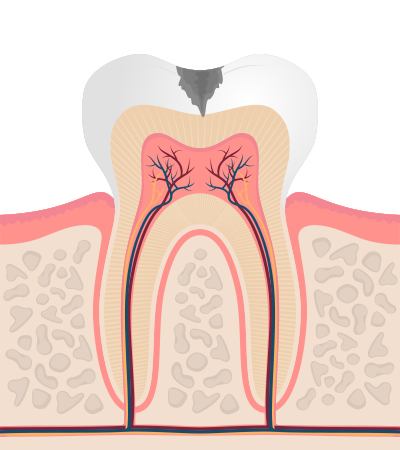

충치의 단계 및 치료법

-

2단계

상아질까지 진행 시리고 약간의 통증